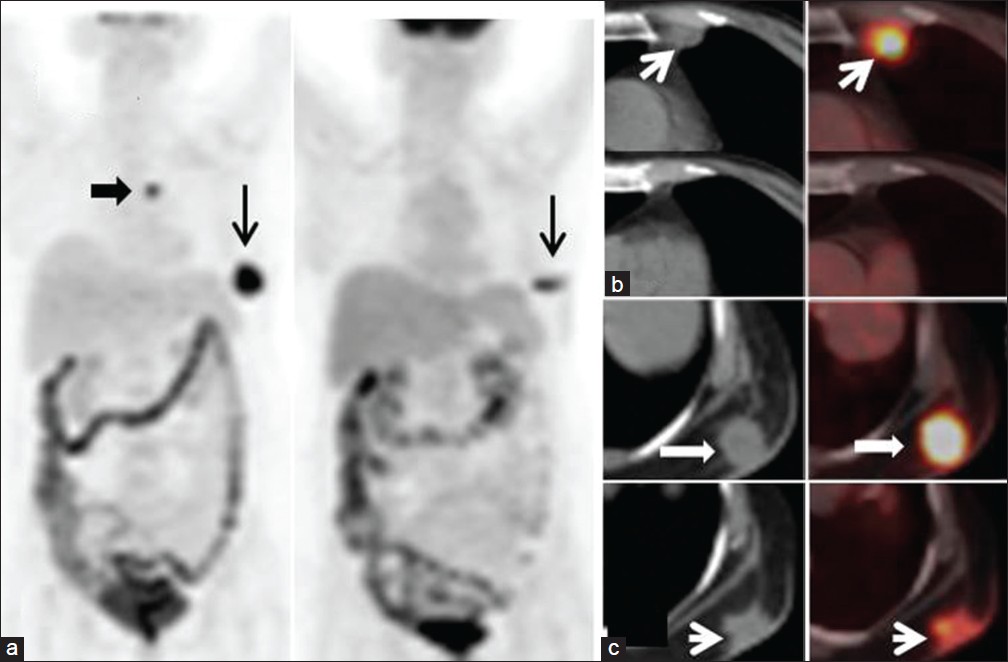

They retrospective analysed whether anatomical (computed tomography [CT]) or functional (positron emission tomography [PET]) imaging be used for response assessment in patients on Metronomic Chemotherapy. A total of 16 males and 27 females (age range of 12-83 years) who were receiving MC and who underwent CT RECIST 1.1 and PET PERCIST 1.0. for response evaluation in solid tumors were reveiwed

Concordance between RECIST 1.1 and PERCIST was seen in 32 (75%) patients. There was discordance in 11 (25%) patients. In patients with discordance, the results were confirmed by follow-up imaging. PET upstaged the disease in 81% of patients (9/11) and down-staged the disease in 19% of patients (2/11).

The authors then conclude taht metabolic response accurately identified the disease status as assessed by clinical or imaging follow-up. As changes in morphology/size takes time to occur, assessing metabolic response by PET would be more appropriate for pateitns receving MC which brings about tumor dormancy.